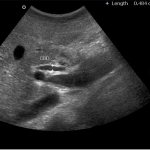

Quite often during pregnancy, after examination by a gynecologist, expectant mothers complain of bleeding from the vagina, which appears literally 10-20 minutes after the procedure. In most cases, this kind of phenomenon is not considered a violation. The thing is that the uterine cervix is ​​very abundantly supplied with blood vessels of various sizes. During the examination, the mucous membrane of this reproductive organ may be injured, as a result of which blood discharge from the vagina is observed.

Several hours after the examination, the patient may experience brown discharge.

• Minor mechanical damage to the inner surface of the cervix caused by a gynecological speculum. Shortly before labor begins, the cervix, which by this time has softened and opened slightly, can be easily injured. With this development of events, the brown discharge will go away as suddenly as it appeared, in a maximum of a couple of days.

• Brown discharge after examination may be the result of a plug coming out - a harbinger of labor activity.

The plug can come off either after inspection by a specialist or without it. During the entire period of pregnancy, the cervix is ​​tightly closed. There is a thick mucus plug in the cervical canal. If the neck is ripe, the plug should come off. This usually happens a few days, and sometimes a few hours before the onset of labor. But there are often cases when it goes away at the moment of the onset of labor, then you may not even notice it.

A plug looks like a clump of mucus, which can be of different colors: white, cream, pink, brown, with or without blood streaks. Its volume is approximately 60 grams (1-2 tablespoons). If a woman is not aware of this phenomenon, then the process of the cork coming out may frighten her.

At 38-39 weeks it is already possible to expect childbirth, so the gynecologist must examine the expectant mother on the chair, assessing the level of preparation of the cervix. The procedure is quite painful and unpleasant, associated with slight trauma to the mucous membranes. Therefore, brown discharge during pregnancy can be considered as bloody discharge resulting from a careless examination. By the way, their color can be not only brown, but also brown and red. However, this is not at all dangerous.

In this case, at 39 weeks of pregnancy, brown discharge appears within a few hours after examination and disappears within a couple of days. Pain and discomfort when the cervix is ​​injured can also be caused during sexual intercourse. The discharge may not go away for two days or more. Therefore, a man should show maximum caution and respect towards a woman.